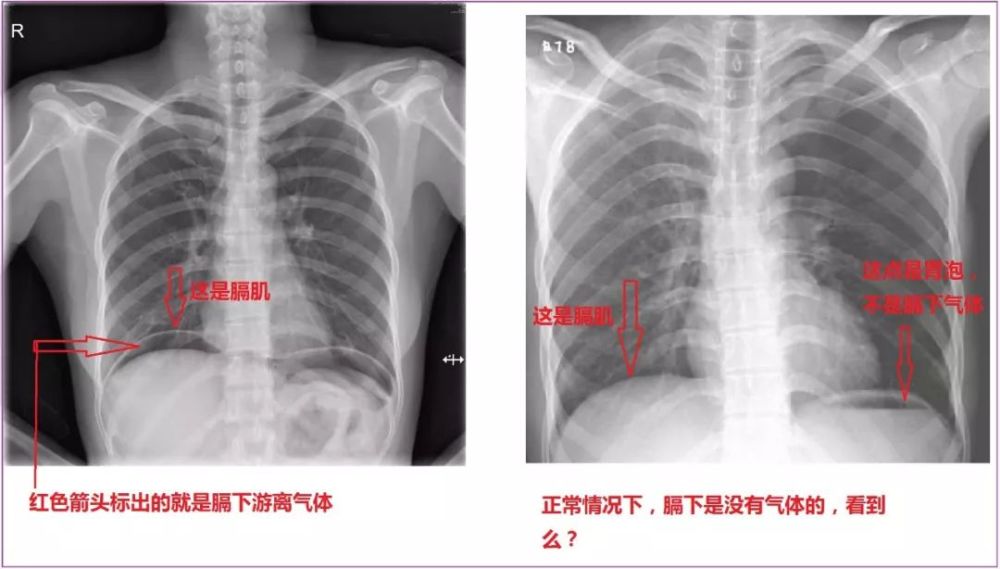

患者既往没有慢性胃病史,临床表现也不像胃穿孔那般剧烈疼痛,腹部平片

入院当天下午起腹胀明显,查腹部平片

(腹腔积气,气腹)消化道溃疡内镜检查后,腹部疼痛.

二,腹部平片